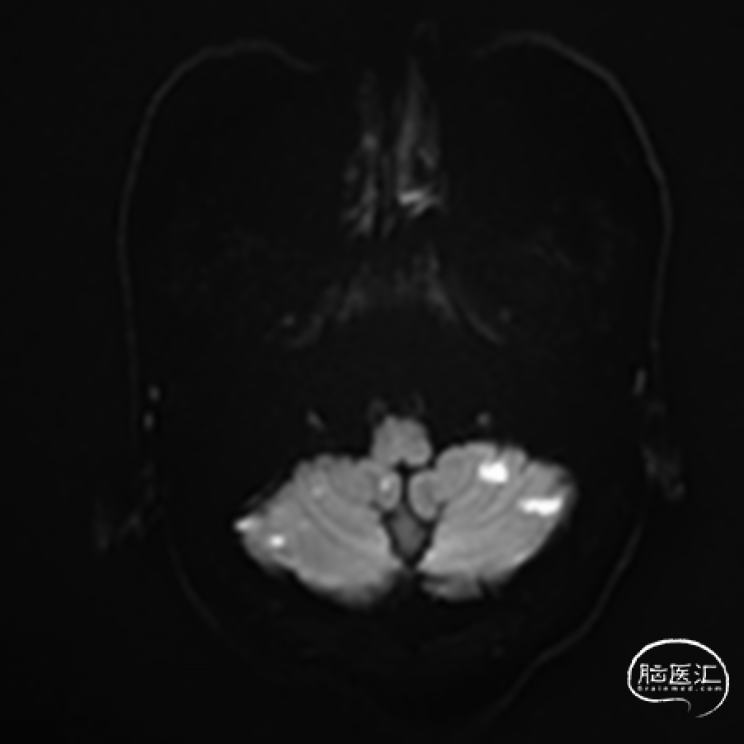

➢2024.07.08 外院颅脑MR提示:

双侧小脑及桥脑多发急性脑梗死,基底动脉闭塞?大脑后动脉狭窄。

➢2024.07.10 MR:

核磁共振提示发病机制穿支事件+低灌注

高分辨核磁提示左侧椎动脉V4段不稳定斑块